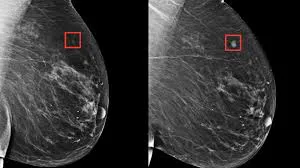

He aquí donde la inteligencia artificial (IA) está emergiendo como una apuesta poderosa, capaz de detectar pequeños signos que podrían pasar desapercibidos en las revisiones tradicionales. Un ejemplo de esta revolución tecnológica es Mia, una herramienta de IA que detecta tumores cancerígenos.

En los últimos meses esta herramienta se ha estado probando en hospitales británicos con resultados sorprendentes. En un estudio reciente, incluso, Mia analizó cerca de 10.000 mamografías, identificando con éxito el cáncer de mama en 11 pacientes que no habían sido diagnosticados por los médicos.

Los expertos presenciaron cómo esta herramienta de IA que detecta tumores cancerígenos señalaba tumores "prácticamente invisibles" al ojo humano, un hecho que abre nuevas posibilidades en la lucha contra esta enfermedad.

Bárbara es una de las 11 pacientes que se benefició con la novedosa herramienta de IA que detecta tumores cancerígenos. En su caso, Mia, identificó un tumor de apenas 6 mm que no había sido detectado por los médicos en las imágenes de su mamografía.